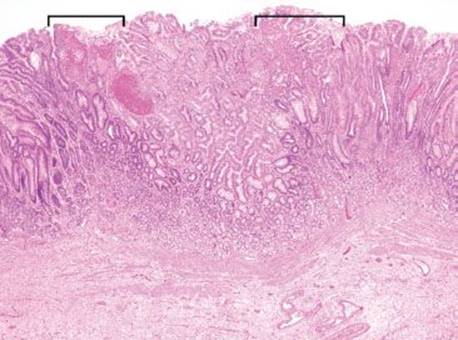

Figure 2.210 PHG. At low power, the predominant finding is that of reactive gastritis/gastropathy pattern of injury: gastric foveolar mucin cell depletion, a corkscrew-like appearance of the foveolar epithelium, lamina propria edema, and little to no inflammation. The reactive gastritis/gastropathy pattern can be a red flag to a variety of additional diagnoses. In this case, scattered congested vessels are seen (arrowheads).